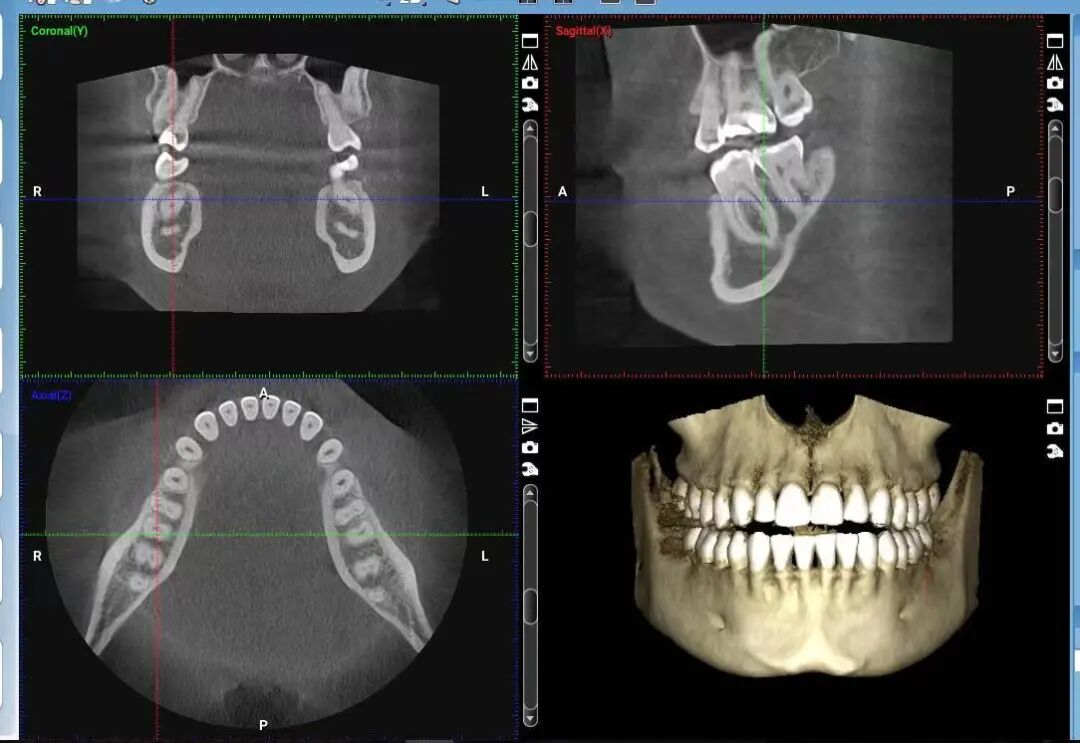

五. 诊断牙周炎需要做哪些检查?